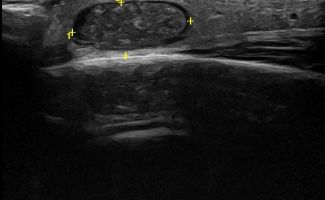

Η τεχνική του Έγχρωμου Doppler μελετάει την αγγείωση της βλάβης. Η τεχνική του Παλμικού Doppler μελετάει την παρουσία αρτηριακών ή φλεβικών στοιχείων εντός της βλάβης. Επίσης πολύ χρήσιμη είναι η Ελαστογραφική Μελέτη η οποία μελετάει τη σκληρότητας της βλάβης. Οι τεχνικές αυτές μας βοηθούν να χαρακτηρίσουμε αν η βλάβη είναι αγγειακού τύπου και αν έχει καλοήθη η ύποπτα χαρακτηριστικά.